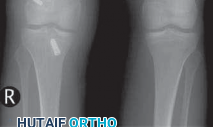

IMAGING AND OTHER DIAGNOSTIC STUDIES

3. Routine radiographs, including weight-bearing anteroposterior and lateral views as well as patellar views, should be performed. In the revision setting, these images allow for critical assesment of previous tunnel placement and assesment for possible bone loss at previous tunnels, which may require further evaluation and treatment.

1. Metallic fixation devices make previous tunnel placement easy to identify, but bioabsorbable screws and other types of fixation also can be evaluated for tunnel placement on these images (

FIG 1

).

2. These images also allow evaluation for possible evidence of osteoarthritis.

FIG 1 • A,B. Anterior cruciate ligament (ACL) reconstruction performed with an EndoButton (Smith & Nephew, Andover, MA) on the femur and staple fixation of the graft on the tibia. C,D. Anterior placement of the femoral tunnel in this primary ACL reconstruction performed with a two-incision technique. A B C

D

13. A common cause of failure related to surgical technique is anterior placement of a femoral tunnel, which often is detected on the lateral radiograph (

FIG 1D

).6,10 This may lead to tightening of the graft with knee flexion resulting in graft stretch-out or failure.